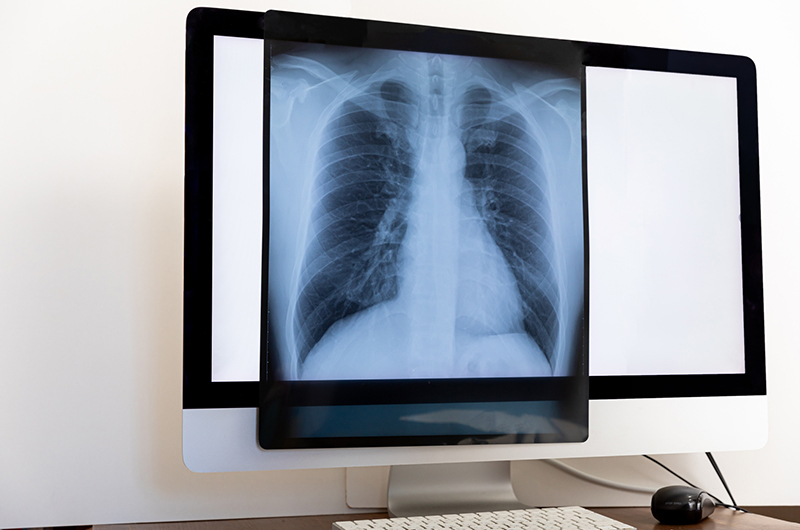

- 胸のレントゲン検査

- 肺に影がないか、また炎症の範囲や程度を確認します。